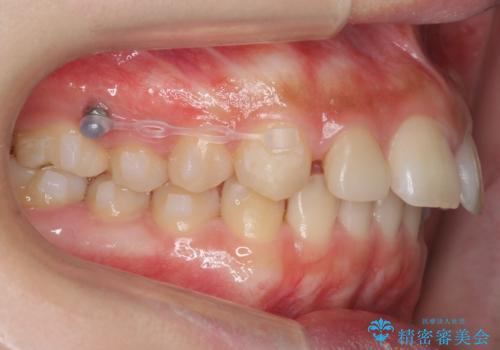

- 前歯の並びを主訴に来院。

前歯が出ており、また、左上の側切歯が1本生まれつき少ない状態でした。

また、右の奥歯の関係も上が前にある状態で大きくずれていました。

臼歯関係は無理に1級にしようとすると抜歯が必要になります。

今回は左右とも1歯対2歯の関係であるため、それは変えずに前歯を可及的にひっこめて足りない部分をブリッジで補う治療としました。

- 104.5万円(マウスピース矯正 93.5万円、矯正用スクリュー11万円) 前歯ブリッジ代は別途費用は治療当時の料金となります

奥歯の関係を完全に1級にするには右上の小臼歯の抜歯が必要でしたが、もともと左上の前歯が生まれつき少ないため今回は歯を抜かずに治療しています。